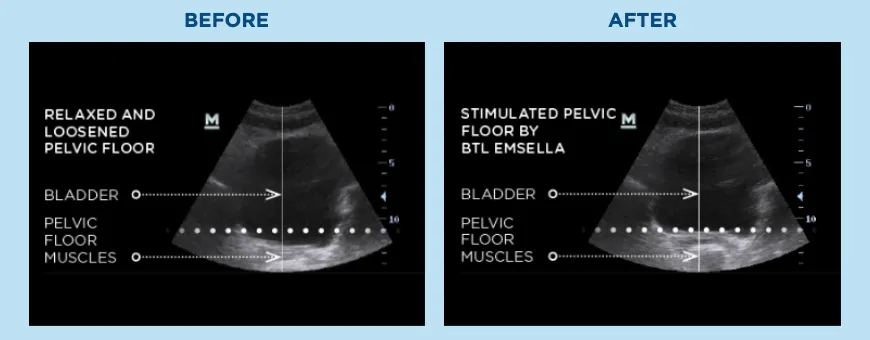

Emsella isn’t just about comfort; it’s about restoring function and strength. Using high-intensity focused electromagnetic energy (HIFEM), it delivers thousands of deep pelvic floor contractions in a single session, far exceeding what can be achieved with traditional exercises like Kegels. These supra-maximal contractions rebuild and strengthen the pelvic floor muscles, improve bladder control, and enhance core stability. The result is not only greater confidence and improved quality of life, but also stronger, healthier muscles that support you in everyday activities.

Emsella combines high-intensity focused electromagnetic (HIFEM) energy with a specially designed chair to target the pelvic floor muscles. The electromagnetic energy penetrates deep into the pelvic region, creating thousands of strong muscle contractions in a single session - something you simply can’t achieve with traditional Kegel exercises.

The real power comes from these supramaximal contractions. They stimulate the pelvic floor muscles at an intensity far beyond what’s possible voluntarily. This extreme stimulus forces the muscles to adapt, strengthening weak tissue, rebuilding muscle fibers, and improving neuromuscular control. The result is a stronger pelvic floor, better bladder control, enhanced core stability, and improved quality of life.